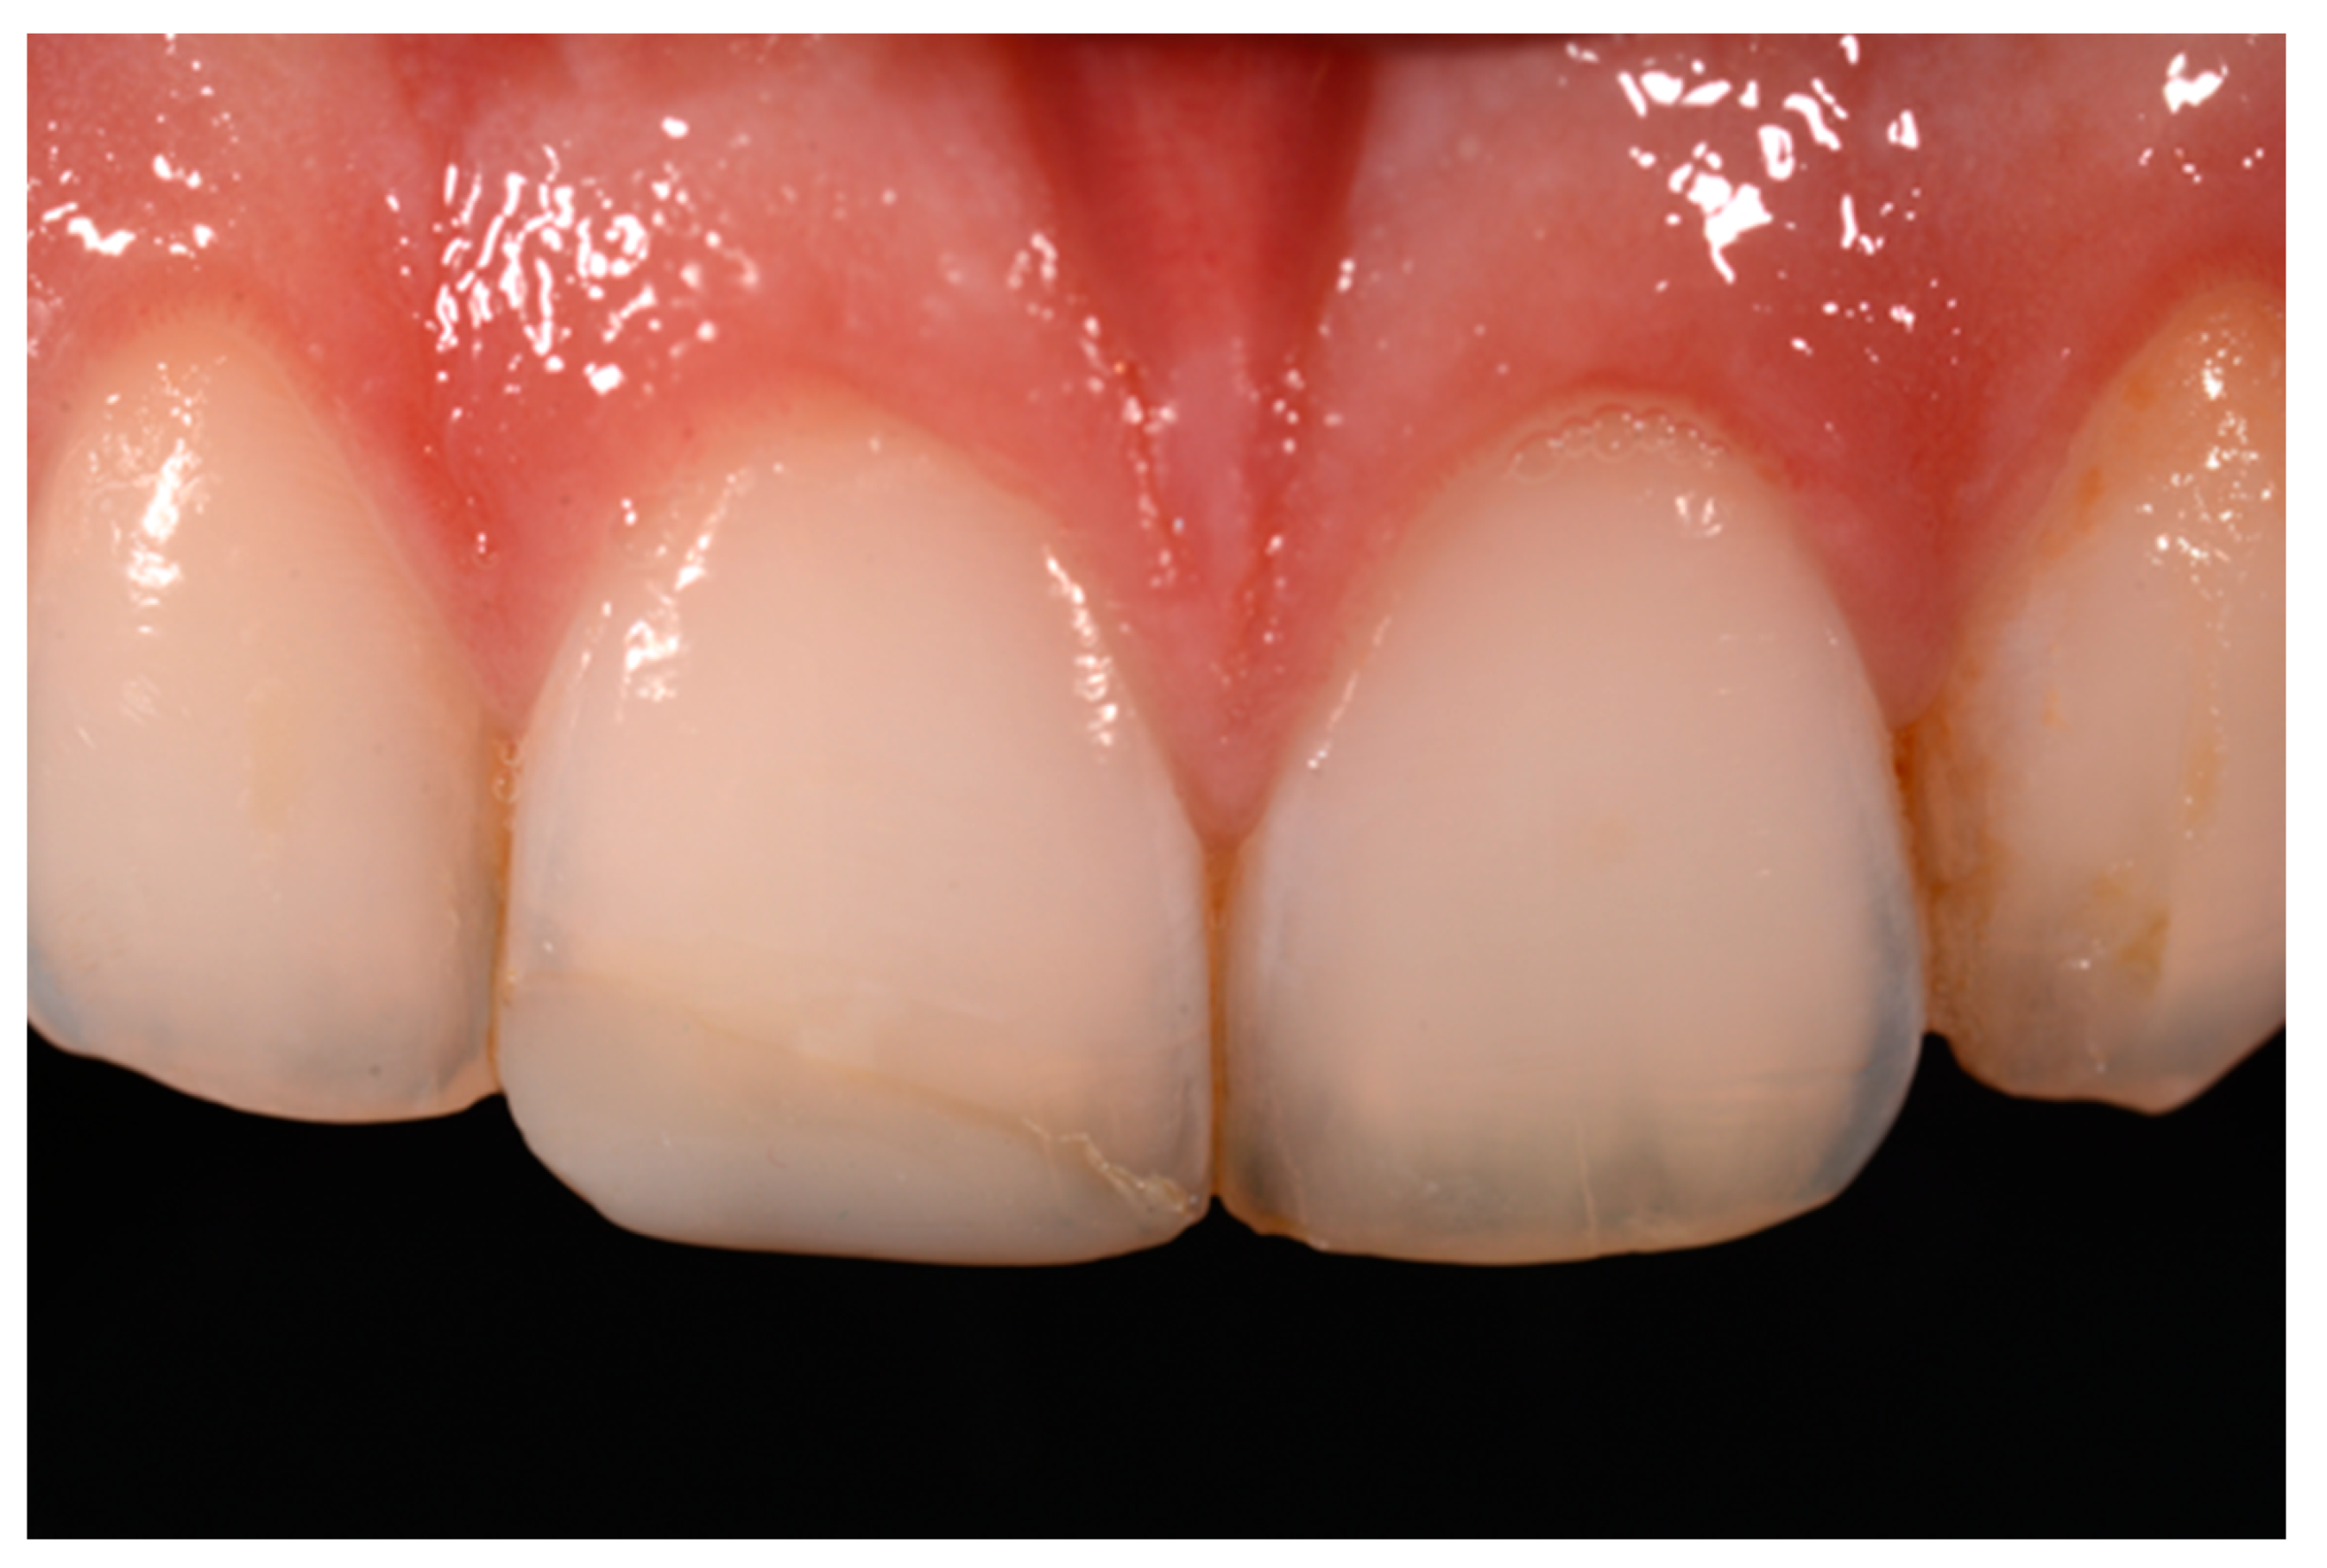

Figure 18.

Five years post-operative.